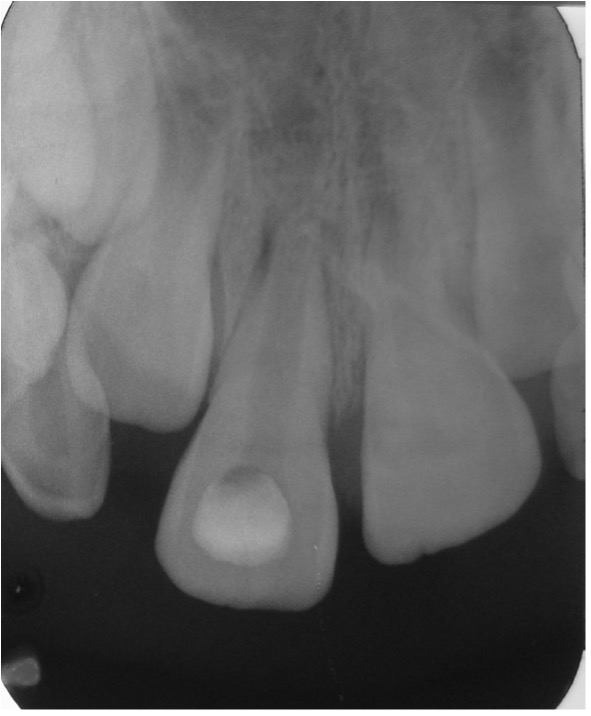

Después de realizada la revascularización y la colocación de la restauración final, se realizaron controles clínicos y radiográficos para evaluar la ausencia de sintomatología y el desarrollo radicular; con lo que se puede concluir que el protocolo utilizado para este caso presentó resultados favorables. Observándose primero un engrosamiento de las paredes del canal radicular a los 04 meses de seguimiento, luego un aumento en su longitud radicular a los 07 meses y un posterior cierre apical a los 14 meses (Figura 11 - 14).

Figura 11: Pza. 11 mostró engrosamiento de las paredes del conducto radicular a los 4 meses post tratamiento.

Figura 12: Pza. 11 muestra aumento de la longitud radicular a los 7 meses post tratamiento.

Figura 13: Pza. 11 se inicia formación del ápice radicular a los 10 meses post tratamiento.

Figura 14: Pza. 11 muestra cierre apical formado a los 14 meses post tratamiento.